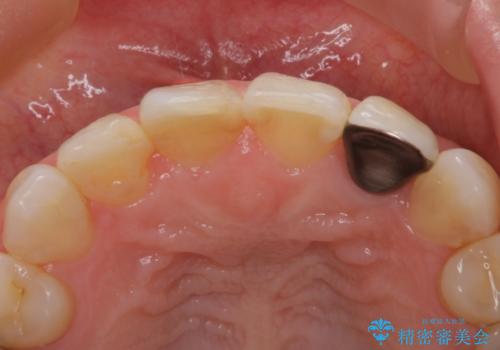

- 患者様は前歯にできものができたということで来院されました。

歯髄診断を行い、失活していると判断して根管治療を行いました。